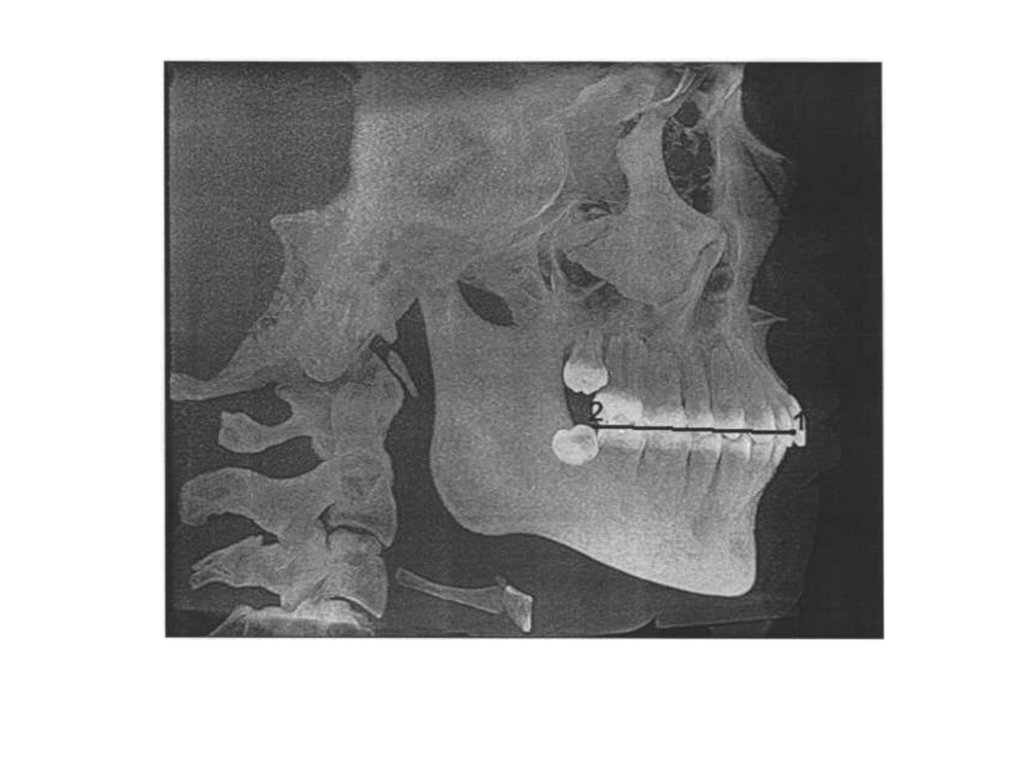

• Под центральной окклюзией понимается

смыкание зубных рядов при максимальном

количестве контактов зубов-антагонистов, при

этом головки ВНЧС находятся у основания ската

суставного бугорка; жевательные мышцы

одновременно и равномерно напряжены.

• При отсутствии антагонирующих пар зубов, при

полном отсутствии зубов - необходимо

определить центральное соотношение.

• При центральном соотношении челюстей

характерно физиологическое расположение

элементов ВНЧС и равномерная нагрузка на все

структуры сустава.